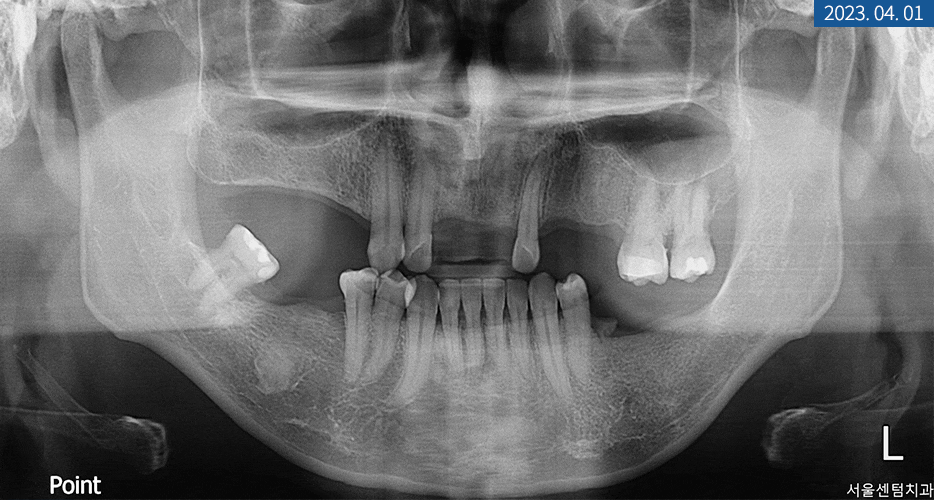

파노라마 엑스레이를 찍어보니

상하악의 영구치가

전체적으로 많이 탈락돼있었습니다.

또한 좌측 상악 어금니에

치통과 더불어 염증 소견이 보여

신경 치료도 동반해야 했는데요.

위 사진의 상태를 갖고 계셨던

40대 남성분께서는 치아 상실이 돼서

저작 기능의 불편을 경험하고 계셨습니다.